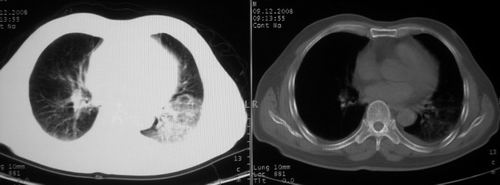

男,78岁,咳嗽、咳痰、发热入院,抗炎治疗一周后已退热,咳血似痰。

10月9日片: